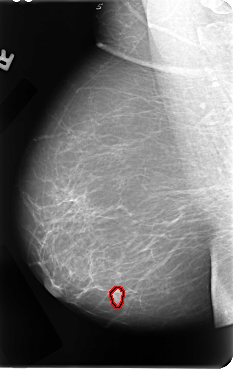

B_3067_1.RIGHT_MLO

RIGHT_MLO LINES 4792 PIXELS_PER_LINE 3024 BITS_PER_PIXEL 12 RESOLUTION 50 OVERLAY

FILE: B_3067_1.RIGHT_MLO.OVERLAY

TOTAL_ABNORMALITIES 1

ABNORMALITY 1

LESION_TYPE MASS SHAPE LOBULATED MARGINS CIRCUMSCRIBED-ILL_DEFINED

ASSESSMENT 4

SUBTLETY 4

PATHOLOGY MALIGNANT

TOTAL_OUTLINES 1

BOUNDARY